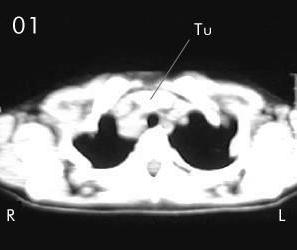

Tomografía torácica

Estudio Tomográfico tórax completo: En detalles los cortes progresivos desde el manubrio esternal hasta 2 cm sub carinal traqueal. (vistas desde el abdomen), (R) = derecho , (L) = Izquierdo; no se apreciaron procesos en pleura ni parenquima pulmonar.

En Mediastino antero superior:

Corte 01: Masa (Tu) densidad de partes blandas anterior lobulada con extensión lateral derecha de la traquea torácica.